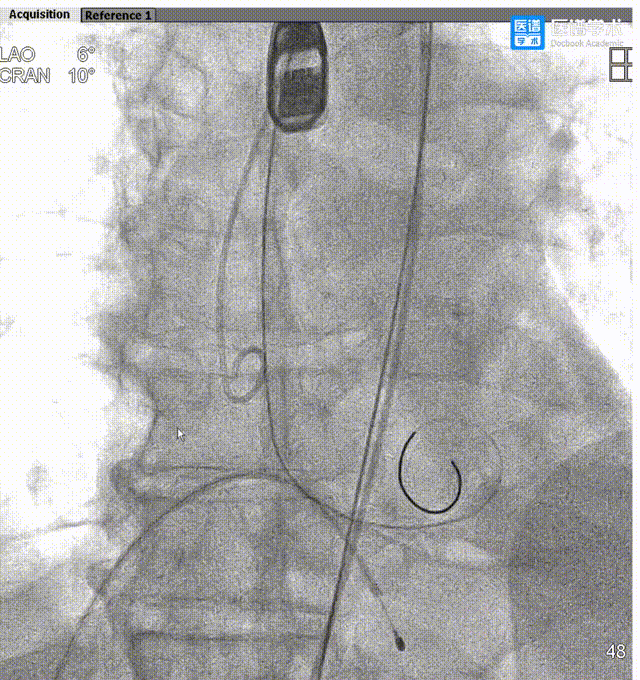

导丝轻松跨瓣

Taurus输送器柔顺的姿态,过弓不伤弓

瓣膜释放,彰显配合精准

瓣膜释放后形态位置良好,造影微量返流